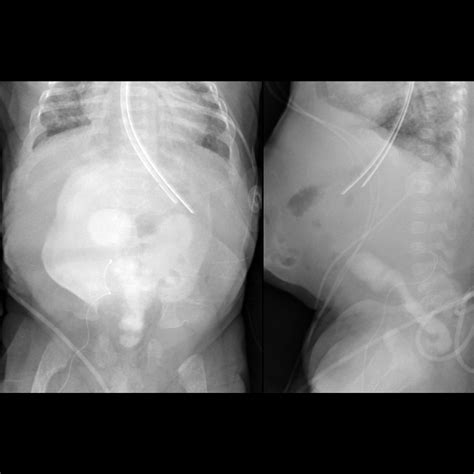

• X-rays: Often the first line of defense for bone fractures or lung issues.

• Fluoroscopy: Used to observe real-time movement, such as how a child swallows or how the gastrointestinal tract functions.